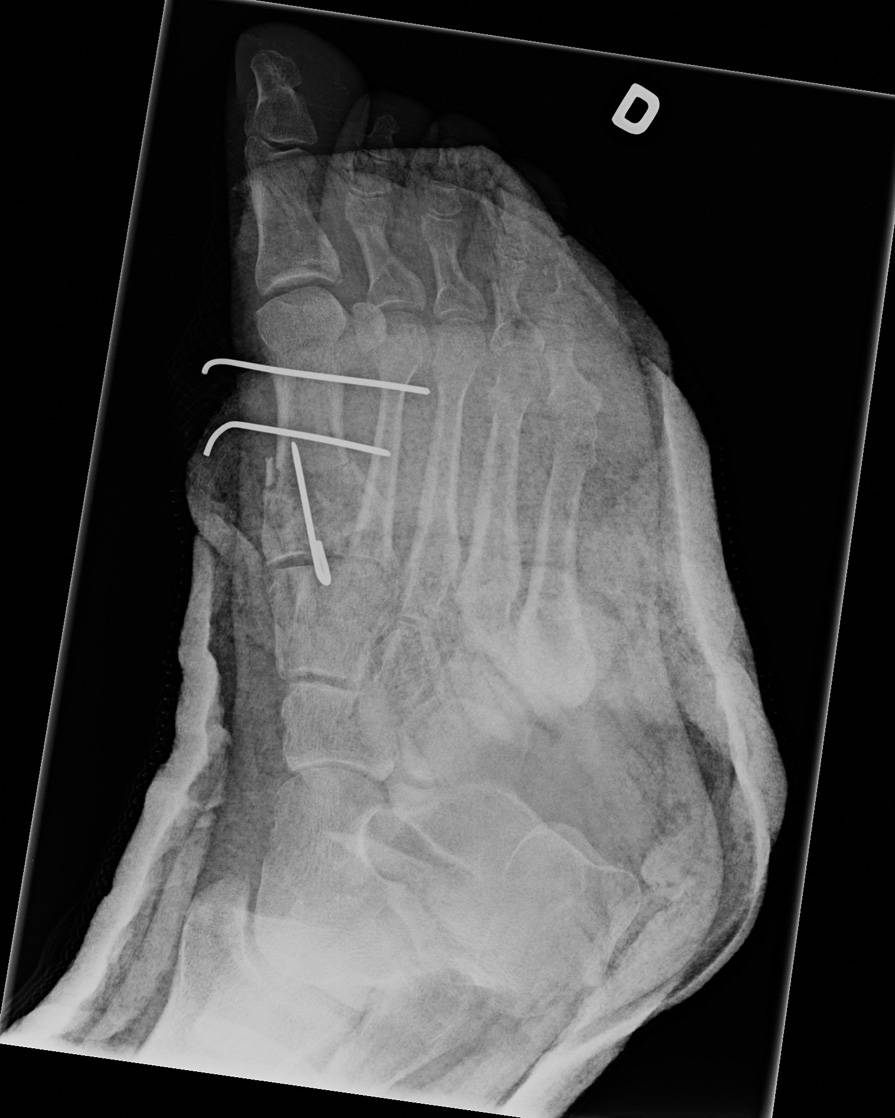

54-year-old male:

Postoperative control of a first metatarsal bone fracture.

Reduction the first metatarsal fracture and fixation of the distal fragment to the second metatarsal with two transverse Kirschner wires.

Metatarsal fracture (1st)

A proximal wire was inserted longitudinaly to fix the base and distal fragments.

1st metatarsal alignment

Postoperative alignment is adequate.